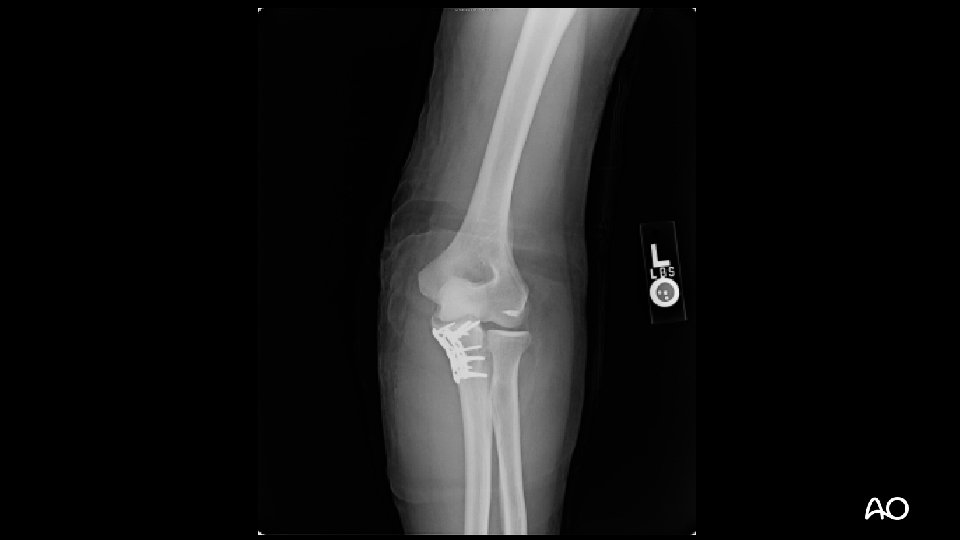

Case 3

Monteggia variant fracture dislocation • Most often posterior dislocations with associated proximal ulnar/olecranon fractures • May have associated radial head fractures • Principles are similar to treatment of standard Monteggia injuries of forearm

Monteggia variant—tactic • Principle: anatomical reduction of ulna is critical for maintenance of radial head reduction • Extensile posterior approach: • Can get to radial head for repair if necessary